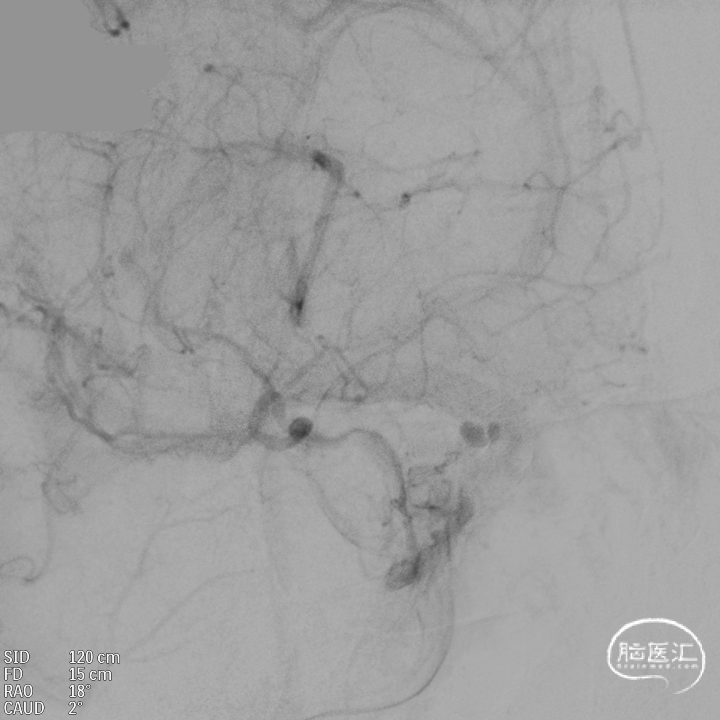

支架内使用成襻微导丝进行按摩,使支架充分贴壁。

术后造影:支架覆盖两枚动脉瘤瘤颈,贴壁良好,瘤体内可见造影剂滞留。

术后支架显影:

术后造影:支架充分覆盖动脉瘤瘤颈,贴壁良好,瘤体内可见造影剂滞留。

术后支架显影:定位精准,未覆盖颞前动脉及大脑前动脉。